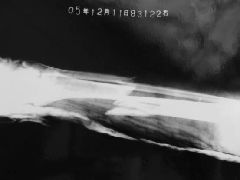

2:再附龚星灿被迫害前与第一次被非法劳教迫害,造成胫腓骨粉碎性骨折保外就医时的前后照片对比(见图片);以及骨折的X光照片(见图片),当时骨头刺破外表皮肤十多公分,缝合了十几针,直到再次被绑架关押时,还有二公分表皮没有好。  骨折的X光照片 |  骨折的X光照片 |